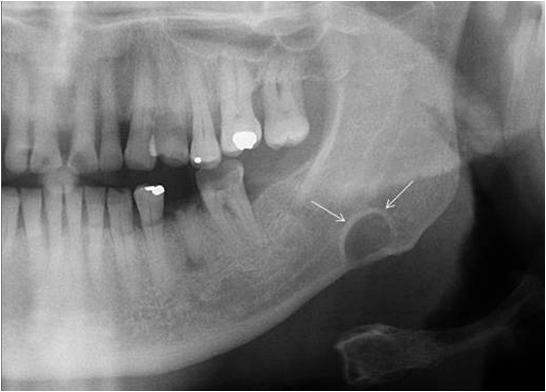

So sieht se aus die Stafne.

Dafür ist das Thema unserer Krankengeschichte recht interessant. Es geht um eine Stafne-Zyste, die eigentlich gar keine Zyste ist, sondern ein gutartigen Knochendefekt im Unterkiefer unterhalb des Mandibularkanals, die durch den Druck der Glandula submandibularis entsteht.